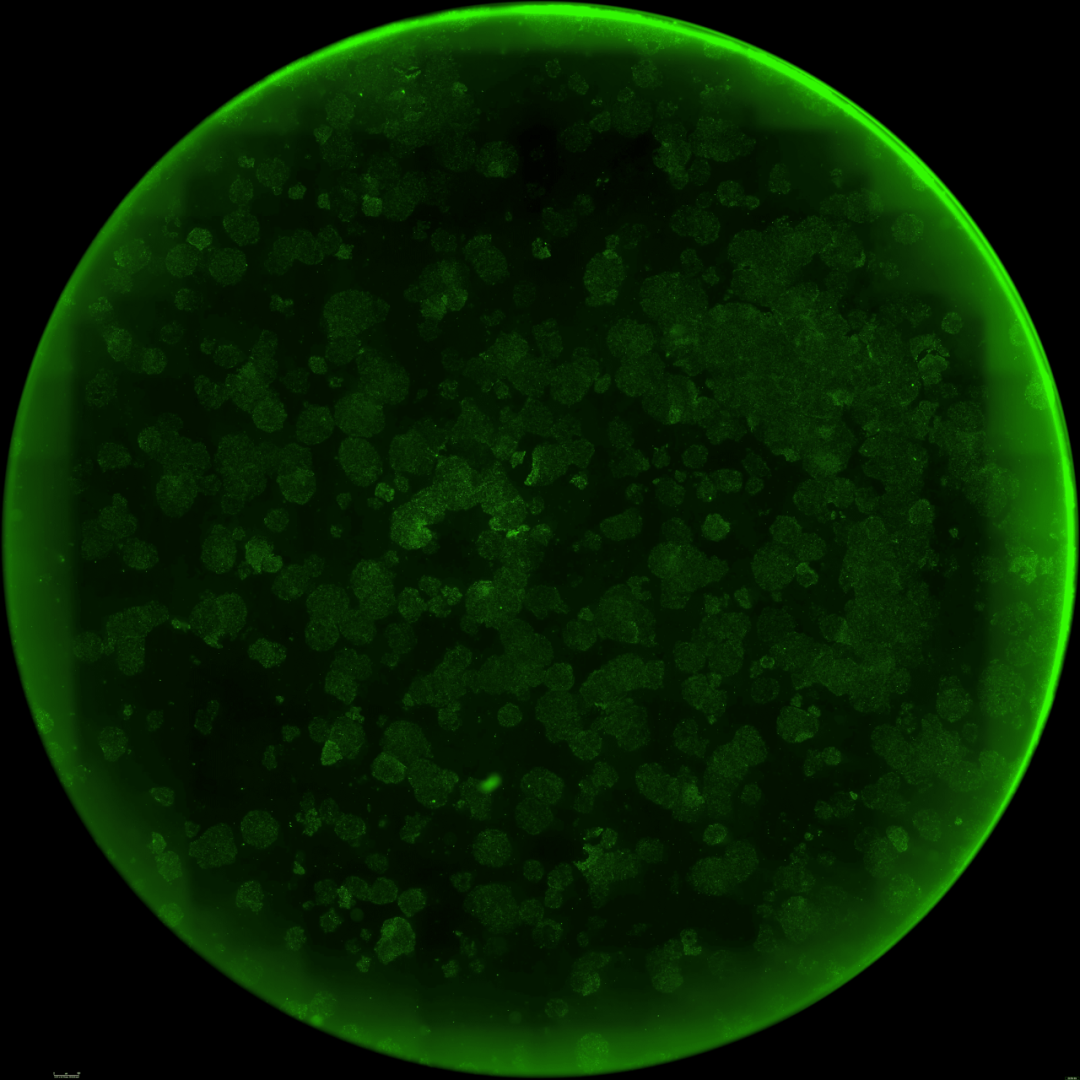

重构变体增强 DNA 损伤修复能力

接下来,OpenAI 进一步探究了这些重构变体的细胞年轻化潜力,并重点考察了它们恢复衰老细胞年轻特征的能力。

现有的研究表明,山中因子可以在不完全逆转细胞身份的前提下,清除小鼠细胞中与 DNA 损伤相关的衰老标记。

那么,与标准的 OSKM 相比,OpenAI 制作的变体是否能表现出更强的年轻化能力呢?

下图所展示的,便是经阿霉素诱导产生 DNA 损伤后,细胞内损伤标记物 γ-H2AX 的强度(越低越好)。

可以看到,与阴性对照组(GFP)和阳性对照组(OSKM)相比,使用 Retro 变体(RS4, RS5)处理的细胞,γ-H2AX 信号有显著的降低。

也就是说,在遭受同等遗传毒性挑战后,RetroSOX / KLF 组合方案比原始的山中因子能更有效地减少 DNA 损伤。